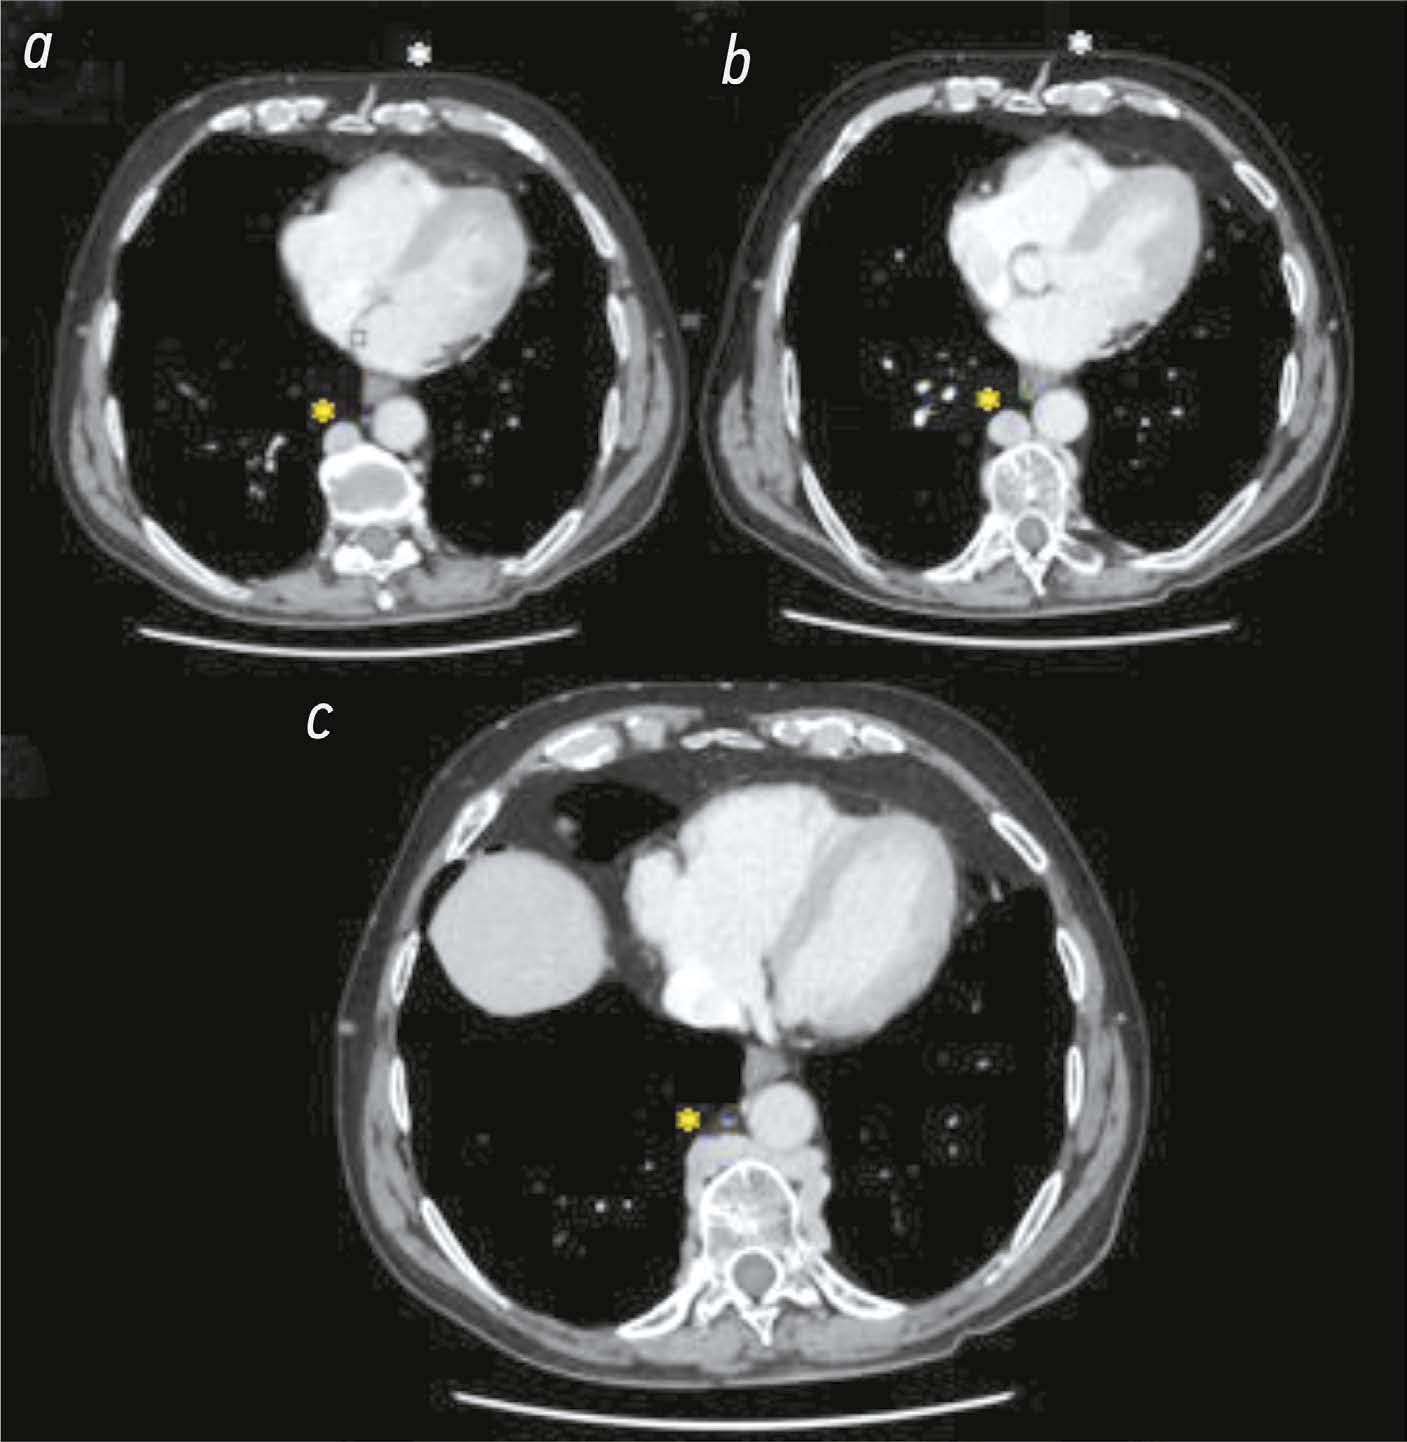

Гипоплазия нижней полой вены — это редкая врождённая сосудистая аномалия, которая отличается разнообразием форм. В некоторых случаях нижняя полая вена прерывается. Именно поэтому поиск описания определённых анатомических вариантов данной аномалии в литературе — это достаточно трудная задача. В настоящей статье представлен уникальный случай бессимптомной гипоплазии инфраренального сегмента нижней полой вены, сопровождающейся гипертрофией непарной и полунепарной вен, а также формированием сети коллатеральных вен на передней брюшной стенке. Сосудистая аномалия выявлена случайно у мужчины 75 лет. Помимо описания клинического случая, в статье кратко охарактеризованы сопутствующие изменения венозной системы брюшной полости, особенно выраженные с правой стороны, а также изменения нижней полой вены и системы непарной вены. В работе также приведено обоснование важности проведения визуализационных исследований для выявления сосудистых аномалий. В представленном клиническом случае визуализация выполнена с помощью компьютерной томографии с многофазным контрастированием, что позволило точно определить наличие сложной сосудистой аномалии. У пациента ранее никогда не возникало симптомов, указывающих на наличие данной аномалии, а проявлявшиеся симптомы, повидимому, не были с ней связаны, поэтому пациенту рекомендовано периодическое наблюдение.